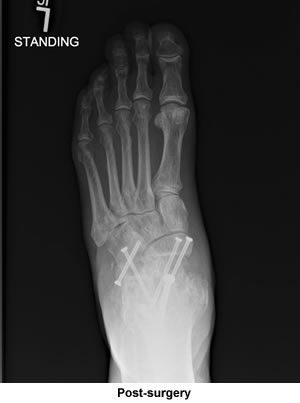

I was all set to have the surgery done elsewhere on just one joint. Casually looking through the Cape Cod Times and spotting your ad for surgery on all sorts of foot problems and stating you were also available for consultation at your office in Bourne immediately convinced me to visit you as I did have some reservations about the surgery I was about to have. I figured that you would confirm that surgery, but that was not the case; you told me three joints were gone and needed fusions. You sent me a very convincing email and also fit me into your surgery schedule much sooner than normally would be expected because of your full workload. I just can't thank you enough for what your surgery has done for me.